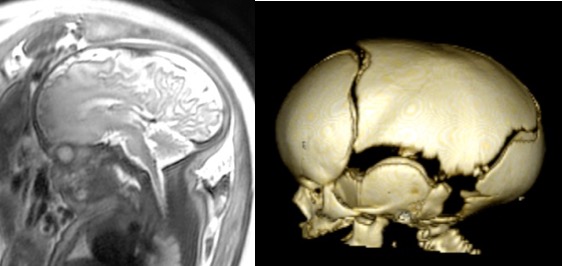

l’IRM

elle permet d’étudier le cerveau, mal vu en échographie

elle est surtout utile dans les brachycéphalies, pour rechercher un retentissement cérébral (engagement tonsillaire, hydrocéphalie) ou d’autres anomalies cérébrales associées (cf. ci-contre : dysplasie orbito-fronto-nasale avec agénésie du corps calleux).